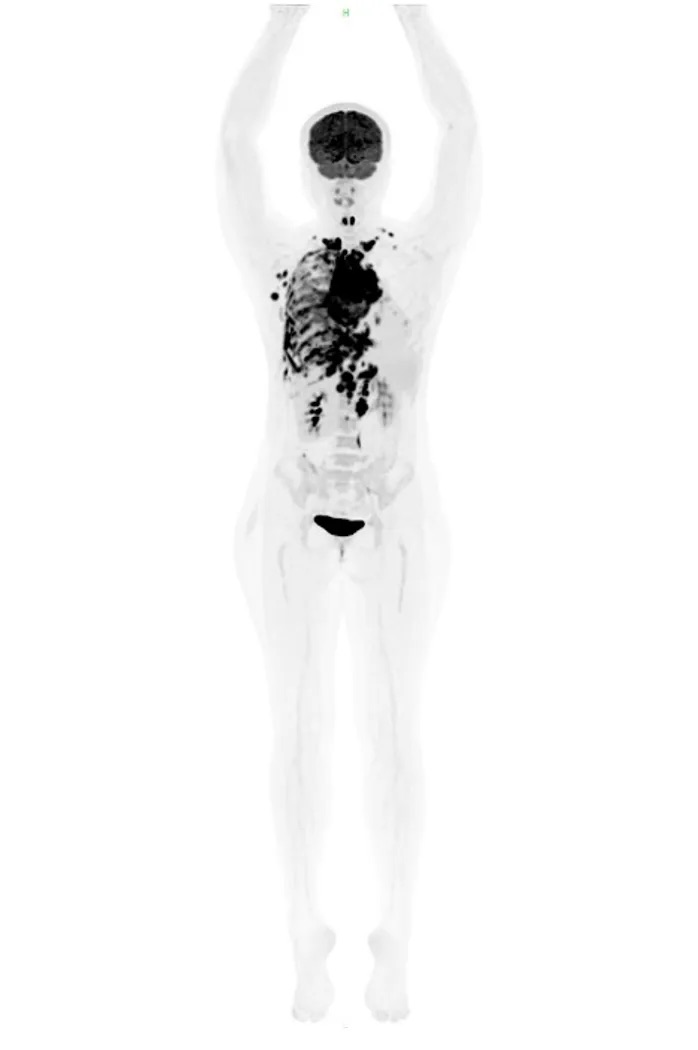

PET-CT(2023年4月3日)(图1)

1. 前纵隔见1个软组织肿块,内见液化死区,代谢明显增高,恶性肿瘤考虑。

2. 肿瘤呈浸润性生长,包绕升主动脉及上腔静脉,并累及相邻右侧纵隔胸膜及心包;纵隔受压左移。

3. 双侧锁骨上窝、双侧下颈部、右侧腋窝、纵隔内、双侧膈肌脚深面、肝胃间隙、中上腹部腹膜后区、胰腺周围、升结肠系膜内见多发肿大淋巴结,代谢增高,多发淋巴结转移灶考虑。

4. 右侧胸膜广泛增厚,代谢明显增高,伴右侧胸腔中至大量积液,右侧胸膜肿瘤广泛转移考虑。

5. 左侧背侧胸膜及纵隔胸膜旁见多处结节状高代谢病灶,伴左侧胸腔少量积液,恶性肿瘤左侧胸膜转移考虑。

图1 患者治疗前的PET-CT检查